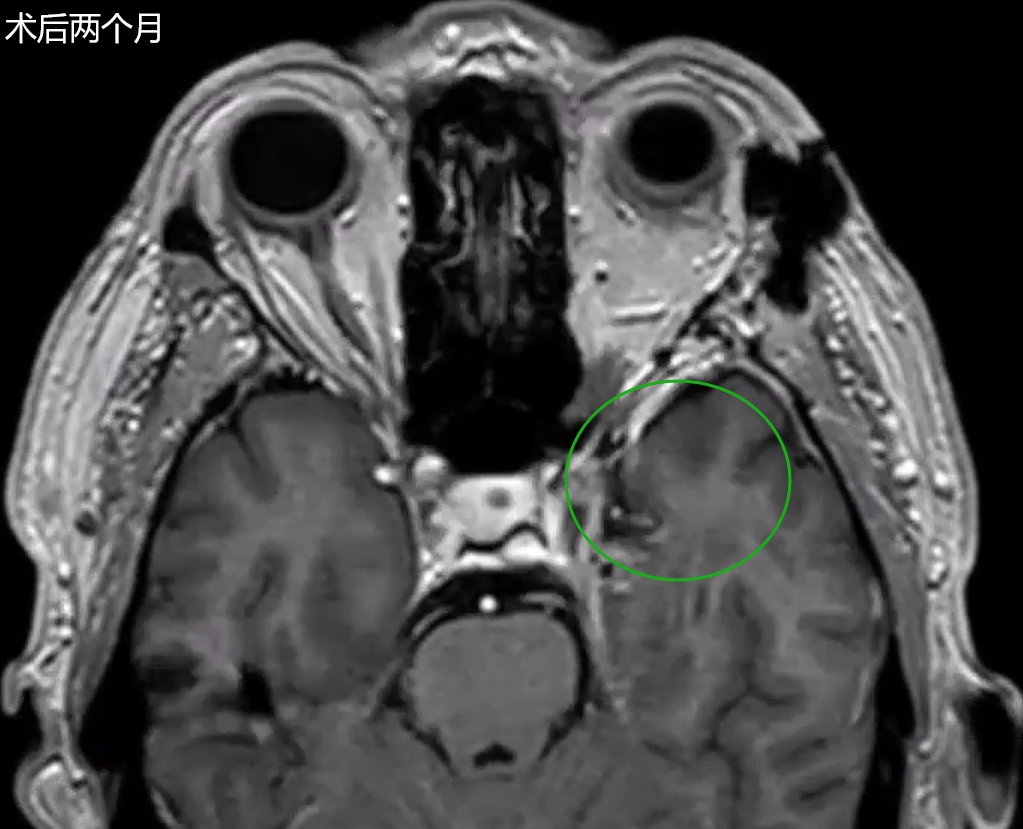

术后影像学复查证实肿瘤获得全切,且未出现任何手术相关并发症。患者未发生新的神经功能缺损,并于术后第6天拆线出院。

术后2个月随访显示,手术疤痕已几乎不可见,成功实现了美容效果与神经功能保护的双重目标。